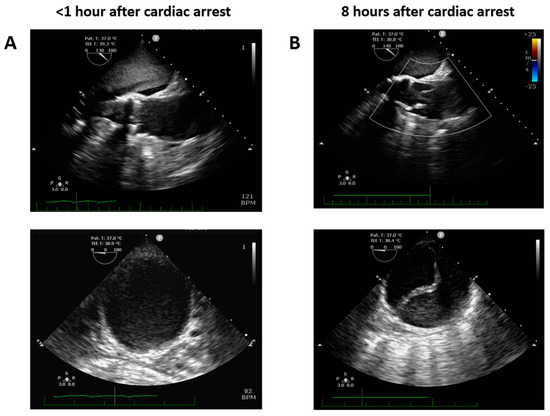

The day of cataract surgery, after premedication (midazolam 3.75 mg and acetazolamide 250 mg orally, and one drop of tropicamide 1% locally), the patient manifested with sudden onset dyspnea accompanied by hypoxemia and elevated systemic arterial pressure (190/120 mmHg). The patient’s status was evaluated as emergent hypertensive crisis with cardiogenic pulmonary edema and was referred to the emergency department. On standard 12-lead electrocardiogram, atrial fibrillation and chronic left bundle branch block were observed (Figure 1). The patient did not react favorably to a standard conservative approach composed of oxygen therapy (delivered by high concentration oxygen mask), intravenously administered loop diuretic (furosemide) and vasodilator (isosorbide dinitrate), and required prompt endotracheal intubation and mechanical ventilation due to ongoing respiratory insufficiency and impaired consciousness (respiratory rate 30 breaths per minute, pulse oximetry peripheral arterial oxygen saturation <50%, Glasgow Coma Scale 8–10 points). Distant inspiratory crackles and an excessive amount of frothy sputum from the endotracheal tube were in agreement with the working diagnosis of cardiogenic pulmonary edema. Immediately following endotracheal intubation, bradycardia and subsequently asystole occurred. Cardiopulmonary resuscitation with advanced life support was initiated using the LUCAS chest compression system (Stryker Medical, Lund, Sweden). Ultrasound performed just before circulatory collapse did not reveal any obvious cause of imminent cardiac arrest, no signs of acute cor pulmonale, pericardial tamponade or any indirect indication of TAD were detected. As cardiac arrest was refractory and the local criteria for extracorporeal cardiopulmonary resuscitation were met, veno-arterial extracorporeal membrane oxygenation (VA-ECMO) was implanted, using a Cardiohelp pump (Getinge, Rastatt, Germany) and standard femoro-femoral cannula configuration (inflow venous 23 Fr, outflow arterial 17 Fr). At the time of circulatory collapse, when the decision to initiate VA-ECMO therapy was made, the arterial level of lactate was 11.8 mmol/L and pH was 6.87. Circulatory collapse to VA-ECMO insertion time was approximately 40 min. Transesophageal echocardiography, used for guidance in VA-ECMO cannula insertion, showed a “standing heart” picture compatible with ongoing pulseless electrical activity, which persisted throughout the entire period of extracorporeal support. Additionally, during approximately the first 8 h on extracorporeal circulatory support, there were still no signs of aortic dissection on transesophageal echocardiography and no intimal flap was detected in the peripheral arteries on regular bedside ultrasound using a vascular probe. Subsequently, the patient became volume-dependent, with decreased systemic vascular resistance, requiring massive fluid resuscitation and high doses of vasopressors to maintain adequate perfusion pressure. Positive crystalloid balance was 4900 mL, positive cumulative fluid balance including colloids and blood derivatives was 10,800 mL. Norepinephrine doses reached 0.7 mcg/kg/min. Regarding initial laboratory blood tests, the patient had normal liver and renal functions, low procalcitonin and C-reactive protein levels, normal total blood cells count with absolute lymphocytosis and relative neutropenia. Plasma level of cardiac troponin I increased from normal value at the time of cardiac arrest to 868,914 ng/L after 12 h, peak value of creatine kinase-MB protein mass was reached 8 h from circulatory collapse (582 mcg/L). After 8 h from cardiac arrest, a clear intimal flap involving the entire length of the thoracic aorta was detected (Figure 2). A conservative therapeutic approach was indicated by the institutional heart team due to poor patient prognosis. VA-ECMO support was withdrawn after 14 h of ongoing pulseless electrical activity. Autopsy revealed Stanford type A TAD causing total obstruction of both coronary arteries, with the entry directly adjacent to the aortic valve prosthesis area (Figure 3). The location of the entry was not typical for spontaneous TAD. No other potential alternative causes of death were identified during autopsy.

Figure 2. Transesophageal echocardiography focused on ascending and descending thoracic aorta performed early (A) and 8 h after cardiac arrest (B).